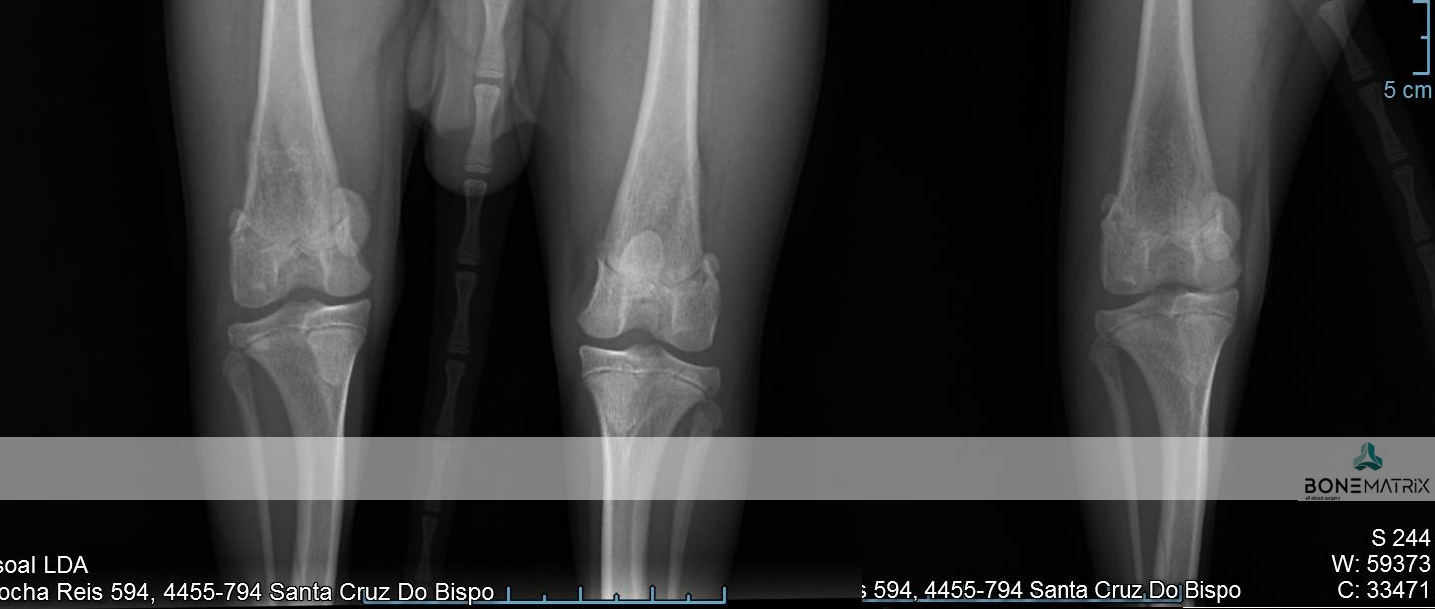

A doença do ligamento cruzado cranial (LCC) é uma patologia degenerativa que pode surgir por influência de fatores genéticos, ambientais ou mecânicos.

O ligamento cruzado cranial é o estabilizador primário do joelho durante o suporte de peso.

É comum a rotura deste ligamento ser uma patologia bilateral (devido à influencia genética) encontrando-se nos dois joelhos mas em estadios diferentes. Por esta razão estudos científicos indicam que 22 a 54% dos cães que apresenta rotura de um LCC diagnosticada irão roturar o contra-lateral em 6 a 17 meses.

O grau de claudicação do paciente está relacionado com a gravidade da patologia (parcial ou total).

Por norma quando existe rotura total ocorre um grau severo de claudicação frequentemente com supressão do apoio. Outros sinais que podem ser detetados clinicamente são um teste de avanço tibial e de gaveta positivos.

A realização de estudo radiográfico poderá servir de apoio ao diagnóstico clínico, nomeadamente através da deteção de inflamação, lesões de osteoartrite e presença de osteófitos.